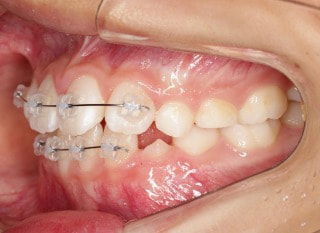

小児期の第二段階

終了時